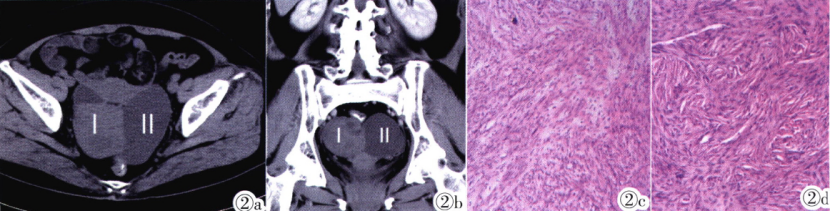

62岁,左侧卵巢单纯性浆液性囊腺瘤并卵泡膜纤维瘤。横断位CT平扫示盆腔囊实性肿块,囊性区域(II)呈单囊改变,内未见分隔,与实性区域(I)分界清楚;图2a:增强扫描静脉期冠状位重建图像示实性成分不均匀轻度强化。图2b:显微镜下卵泡膜纤维瘤示肿瘤细胞呈梭形及短梭形,细胞排列呈“羽毛状”或“编织状”;(HE)图2c:单纯性浆液性囊腺瘤示囊壁被覆单层柱状上皮,无明显异型性(HE)(图2d)。